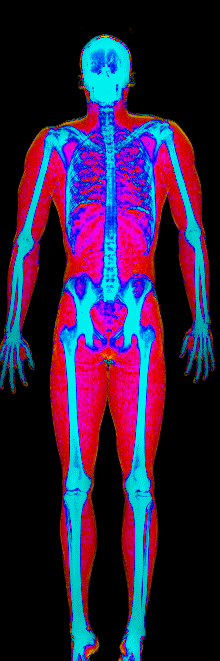

This page features real, anonymized DEXA scan images from BodyStats clients, organized by gender and body fat percentage in 5% increments. DEXA (Dual-Energy X-ray Absorptiometry) is the clinical gold standard for measuring body composition — far more accurate than scales, calipers, or visual estimates.

Each colorized scan shows the distribution of fat tissue (shown in warmer colors) and lean tissue (cooler colors) throughout the body. Compare your own DEXA scan to others in your range, or see what different body fat levels actually look like on a scan.

Male DEXA Scans by Body Fat %

20 to 25% body fat